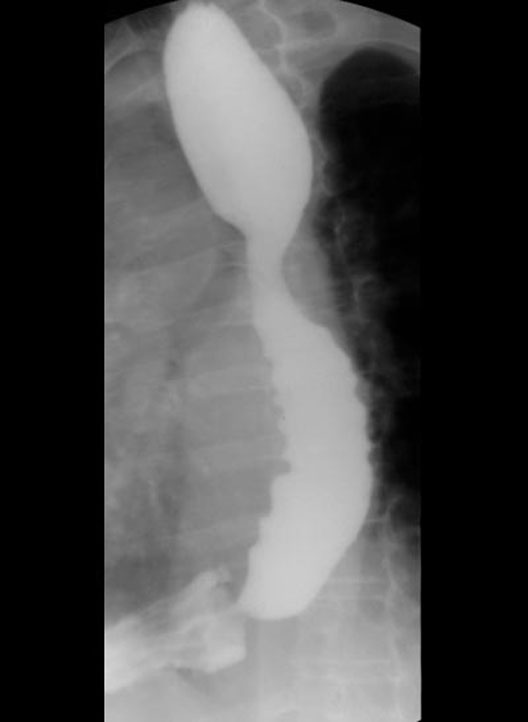

Barium Swallow

1. Lesser Curvature

2. Pyloric antrum

3. First part of duodenum

4. Fundus of stomach

5. Body of stomach

6. Greater curvature

7. Pyloric orifice